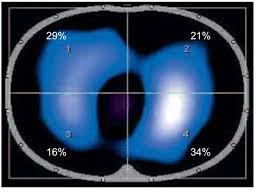

Η αρχή της τομογραφίας εμπέδησης βασίζεται στον υπολογισμό και στις μεταβολές της σύνθετης αντίστασης του ανθρώπινου σώματος σε μια εγκάρσια διατομή, η οποία μετράται με τη βοήθεια 16 ηλεκτροδίων. Τα ηλεκτρόδια είναι τοποθετημένα γύρω από το επίπεδο της εγκάρσιας διατομής που πρόκειται να μελετηθεί, ενώ η ανασύνθεση της εικόνας αναπαράγεται σε monitor το οποίο διαθέτει ο τομογράφος. Όταν εφαρμόζεται εναλλασσόμενο ρεύμα γνωστής έντασης μεταξύ δύο ηλεκτροδίων δημιουργείται ηλεκτρική δραστηριότητα μεταξύ τους.

Η ηλεκτρική αυτή δραστηριότητα καταγράφεται ως διαφορά δυναμικού από τα υπόλοιπα 13 ζεύγη ηλεκτροδίων τα οποία κατανέμονται κυκλοτερώς στην επιφάνεια της νοητής διατομής που μελετάται. Έτσι, σχηματίζεται εναλλασσόμενο ηλεκτρικό πεδίο, οι δυναμικές γραμμές του οποίου διαπερνούν εγκάρσια το μελετώμενο ανατομικό τμήμα. Κάθε φορά που οι δυναμικές γραμμές του εναλλασσόμενου ηλεκτρικού πεδίου διέρχονται από μια περιοχή η οποία δεν είναι συμπαγής, αυτή εκλαμβάνεται ως περιοχή μεγάλης αντίστασης και απεικονίζεται από τον τομογράφο με λευκό χρώμα.

Στη συνέχεια από τις μετρήσεις αυτές είναι δυνατός ο υπολογισμός των τιμών των ηλεκτρικών αντιστάσεων εντός του εξεταζόμενου οργάνου με την τεχνική της οπισθοπροβολής (backprojection), ενώ με τη βοήθεια ειδικού προγράμματος του ηλεκτρονικού υπολογιστή καθίσταται δυνατή η δημιουργία εικόνας, που είναι εικόνα κατανομής της αγωγιμότητας. Ο υπολογιστικός ανασυνδυασμός των 208 διαφορετικών διαφορών δυναμικού που προκύπτουν, μετά και την εφαρμογή ειδικών φίλτρων, συνθέτει μια εικόνα 32×32 εικονοστοιχείων τα οποία οπτικοποιούν τις μεταβολές της σύνθετης αντίστασης της μελετώμενης περιοχής. Μάλιστα, επειδή η ειδική αγωγιμότητα εξαρτάται από την συχνότητα, για κάθε εφαρμογή ηλεκτρικού ρεύματος συγκεκριμένης συχνότητας προκύπτει και διαφορετική εικόνα της κατανομής της ηλεκτρικής αγωγιμότητας, γεγονός που αξιοποιούν οι ειδικοί για την λήψη πολλών διαφορετικών εικόνων με εφαρμογή διαφορετικών συχνοτήτων ρεύματος.

Η αρχή της τομογραφίας εμπέδησης βασίζεται στον υπολογισμό και στις μεταβολές της σύνθετης αντίστασης του ανθρώπινου σώματος σε μια εγκάρσια διατομή, η οποία μετράται με τη βοήθεια 16 ηλεκτροδίων. Τα ηλεκτρόδια είναι τοποθετημένα γύρω από το επίπεδο της εγκάρσιας διατομής που πρόκειται να μελετηθεί, ενώ η ανασύνθεση της εικόνας αναπαράγεται σε monitor το οποίο διαθέτει ο τομογράφος. Όταν εφαρμόζεται εναλλασσόμενο ρεύμα γνωστής έντασης μεταξύ δύο ηλεκτροδίων δημιουργείται ηλεκτρική δραστηριότητα μεταξύ τους.

Η ηλεκτρική αυτή δραστηριότητα καταγράφεται ως διαφορά δυναμικού από τα υπόλοιπα 13 ζεύγη ηλεκτροδίων τα οποία κατανέμονται κυκλοτερώς στην επιφάνεια της νοητής διατομής που μελετάται. Έτσι, σχηματίζεται εναλλασσόμενο ηλεκτρικό πεδίο, οι δυναμικές γραμμές του οποίου διαπερνούν εγκάρσια το μελετώμενο ανατομικό τμήμα. Κάθε φορά που οι δυναμικές γραμμές του εναλλασσόμενου ηλεκτρικού πεδίου διέρχονται από μια περιοχή η οποία δεν είναι συμπαγής, αυτή εκλαμβάνεται ως περιοχή μεγάλης αντίστασης και απεικονίζεται από τον τομογράφο με λευκό χρώμα.

Στη συνέχεια από τις μετρήσεις αυτές είναι δυνατός ο υπολογισμός των τιμών των ηλεκτρικών αντιστάσεων εντός του εξεταζόμενου οργάνου με την τεχνική της οπισθοπροβολής (backprojection), ενώ με τη βοήθεια ειδικού προγράμματος του ηλεκτρονικού υπολογιστή καθίσταται δυνατή η δημιουργία εικόνας, που είναι εικόνα κατανομής της αγωγιμότητας. Ο υπολογιστικός ανασυνδυασμός των 208 διαφορετικών διαφορών δυναμικού που προκύπτουν, μετά και την εφαρμογή ειδικών φίλτρων, συνθέτει μια εικόνα 32×32 εικονοστοιχείων τα οποία οπτικοποιούν τις μεταβολές της σύνθετης αντίστασης της μελετώμενης περιοχής. Μάλιστα, επειδή η ειδική αγωγιμότητα εξαρτάται από την συχνότητα, για κάθε εφαρμογή ηλεκτρικού ρεύματος συγκεκριμένης συχνότητας προκύπτει και διαφορετική εικόνα της κατανομής της ηλεκτρικής αγωγιμότητας, γεγονός που αξιοποιούν οι ειδικοί για την λήψη πολλών διαφορετικών εικόνων με εφαρμογή διαφορετικών συχνοτήτων ρεύματος.